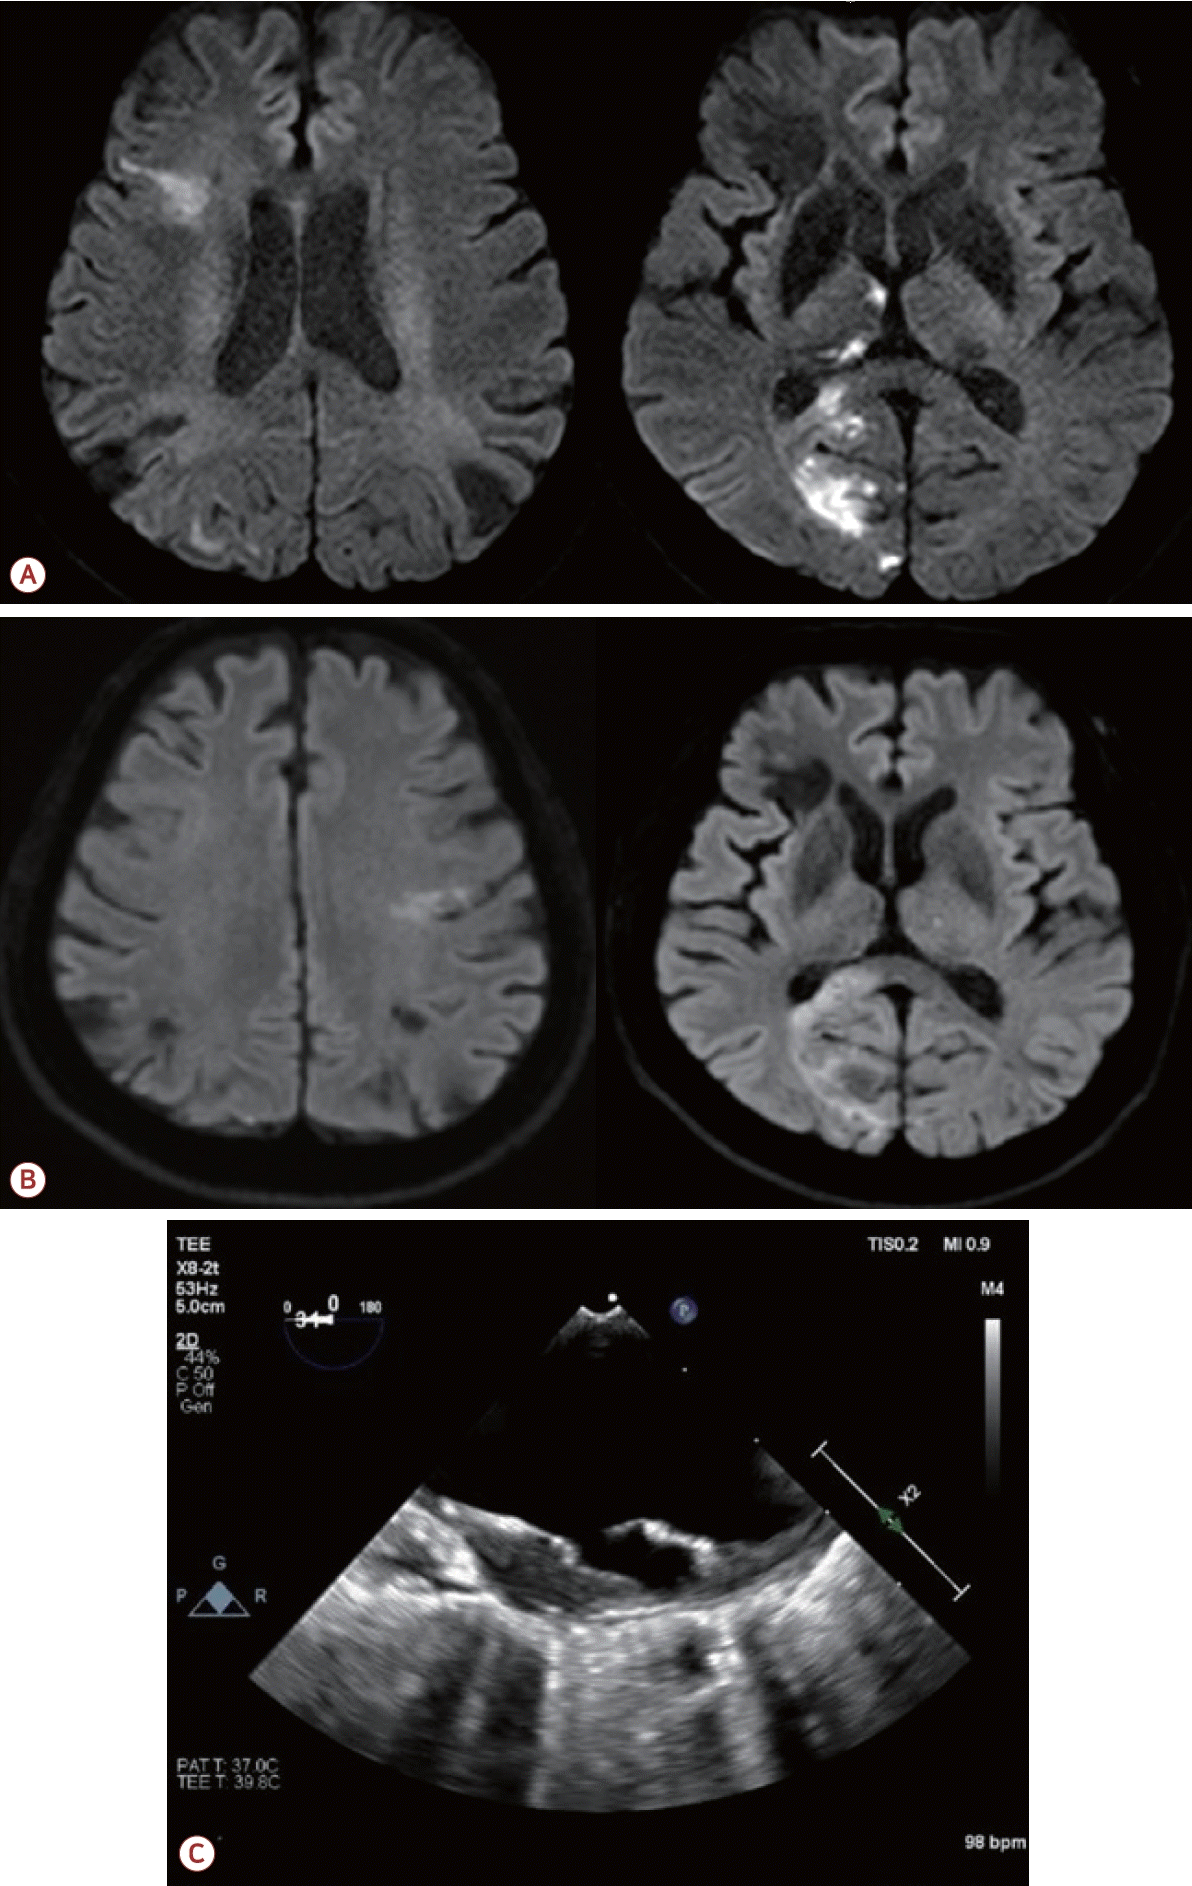

73세 남자가 최근 3개월간 반복적인 허혈뇌졸중으로 내원하였다. 환자는 고혈압, 당뇨, 안정협심증의 기저 질환을 가지고 있었다. 초기 뇌자기공명영상(magnetic resonance [MR] imaging)에서 좌측 대뇌반구와 우측 소뇌에 다발성 허혈 병변이 관찰되었으며(Fig. 1-A) 혈관 검사에서는 좌측 내경동맥근위부(internal carotid artery, ICA)에 76.7%의 협착(NASCET 기준)이 확인되었고 동시에 보바인형 대동맥궁(bovine arch, 공통 기시형 변이)이 관찰되었다(Fig. 1-B). 이에 따라 증상성 중증도 이상의 ICA 협착으로 판단하여 좌측 CEA와 이중 항혈소판 요법이 시행되었다. 그러나 시술 2개월 후에 우측 후 대뇌동맥(posterior cerebral artery, PCA)과 우측 중대뇌동맥(middle cerebral artery, MCA) 영역에 재발성 뇌경색이 발생하였고(Fig. 2-A) 한 달 후에는 좌측 MCA와 PCA 영역에 새로운 뇌경색이 재발하였다(Fig. 2-B). 기존에 진행되었던 두개경유도플러 검사에서 심방중격 결손이나 미세색전 신호를 시사하는 소견은 확인되지 않았고 흉부경유심초음파에서 좌심실 박출률은 정상 범위었으며 3일의 홀터 모니터링에서도 심방세동은 관찰되지 않아 심장성 색전은 배제하였다. 반복되는 색전성 병변의 원인을 찾기 위하여 식도유심초음파(transesophageal echocardiography, TEE)가 진행되었으며 대동맥궁 대만부(greater curvature)에 위치한 7 mm 크기의 궤양성(ulcerated), 유동성(mobile)의 고위험 죽경화판(high-risk aortic arch plaque)이 관찰되었다(Fig. 2-C). 추가적인 머리 혈관조영에서는 기존에 확인되었던 좌측 경동맥의 중증도 협착은 호전 상태를 보였으며 보바인형 대동맥궁 및 팔머리동맥에 동맥류성 확장(aneurysmal dilatation)을 확인할 수 있었다(Fig. 3-A). 이에 신경과, 순환기내과, 영상의학과, 심장혈관흉부외과가 포함된 다학제 협의를 통해 단계적 하이브리드 치료가 결정되었다. 첫 번째 단계로 부분 디브랜칭 수술(좌쇄골하-좌총경동맥우회술[partial debranching surgery, left subclavian-left common carotid artery bypass])이 시행되었다. 수술 한 달 후에 팔머리동맥에 스텐트이식편(endovascular brachiocephalic stent-graft)을 삽입하여 팔머리동맥류의 병적 분절을 제거하였다(Fig. 3-B, C). 스텐트 시술 이후 약 1년 6개월이 지난 현재까지도 환자는 지속적으로 이중항혈소판 요법을 유지하면서 추가적인 허혈 사건 없이 안정적으로 추적 관찰 중이다.

Figure 2.

(A) Two-month follow-up brain MRI showing recurrent cerebral infarction of right PCA and right MCA territories. (B) Subsequent brain MRI showing new infarctions in the left MCA and right PCA territories. (C) TEE revealing a 7 mm mobile ulcerative plaque at the greater curvature of the aortic arch. MRI; magnetic resonance imaging, PCA; posterior cerebral artery, MCA; middle cerebral artery, TEE; transesophageal echocardiography.